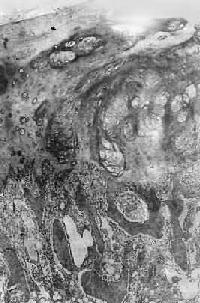

图1-13 初级溶酶体

图中央及中下方之卵圆形电子致密小体,外围单层包膜。(图中及下部片层状膜性结构为粗面内质网(正常肝细胞)